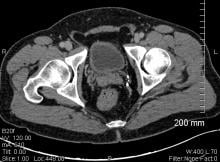

Atherosclerosis is usually considered to be related to contemporary risk factors such as smoking, obesity and lack of exercise. However, researchers suggest that high prevalence of atherosclerosis in pre-modern humans may support the possibility of a more basic human predisposition to the disease.